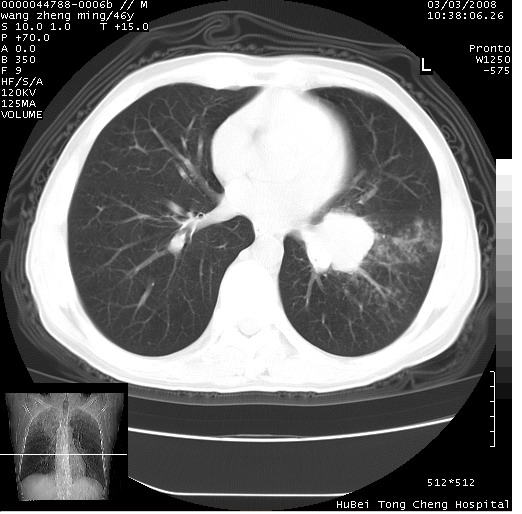

以下是引用卜一在2008-3-22 1:37:00的发言:[br]右肺实质性肿块,边缘不整,明显见毛刺征 分叶征及胸膜凹陷征,右上叶支气管明显变窄,远端散在的片状 斑片状实变影。另:左肺门较大肿块,支气管受累 变窄,远侧见阻塞性肺炎。纵隔内见肿大淋巴结。多考虑:右肺周围性肺癌伴左肺门 纵隔淋巴结转移!